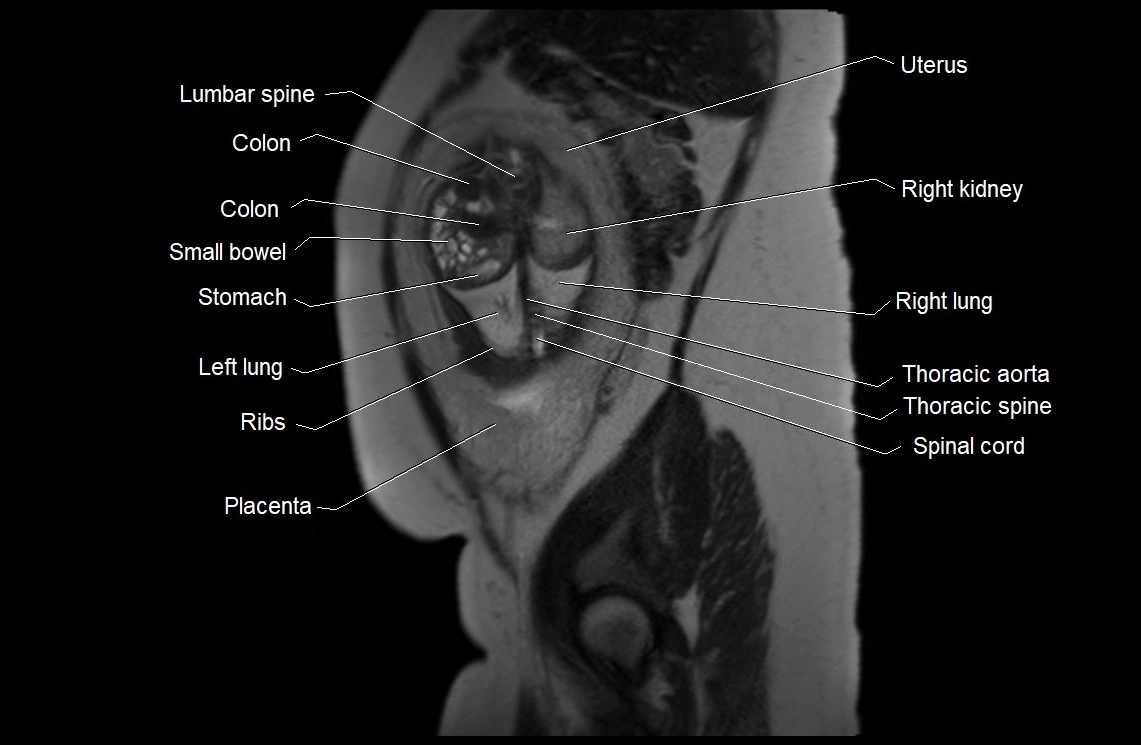

MRI Appearance

T2 HASTE (T2 GRE):

• Amniotic fluid shows very bright hyperintense signal

• Provides natural contrast against fetus and placenta

• Small particles (vernix) may appear as scattered hypointense foci within bright fluid

MRI image

image